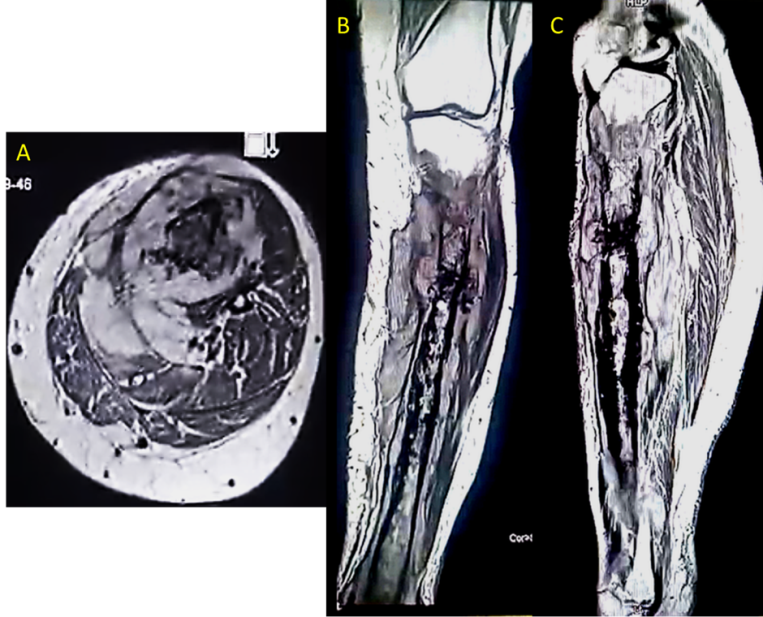

Baseline blood investigations revealed hemoglobin 12 g/dL, leukocyte count 5,000/mm3, platelets 210,000/mm3, erythrocyte sedimentation rate 30 mm/h, and C-reactive protein 5.8 mg/L. Radiographs of the left tibia showed a mixed lytic–sclerotic lesion with cortical breach and periosteal reaction (Fig. 2). Magnetic resonance imaging demonstrated an ill-defined metaphyseal lesion with marrow replacement, cortical destruction, soft-tissue extension, and pathological fracture (Fig. 3). Core needle biopsy suggested a hematolymphoid malignancy, confirmed by open biopsy showing diffuse large atypical lymphoid cells (Fig. 4). Immunohistochemistry revealed diffuse CD45 and CD20 positivity, scattered CD3 positivity, and high Ki-67 (~60%) with cytokeratin negativity (Fig. 5). Positron emission tomography-computed tomography (PET-CT) revealed an avid mass in the proximal tibia with metabolically active regional nodes. Cultures were sterile.

Figure 3: Pre-operative magnetic resonance imaging of the left proximal tibia – (a) axial, (b) coronal, and (c) sagittal T2-weighted images – demonstrating a heterogeneous hyperintense marrow lesion with cortical breach and soft-tissue extension along the anteromedial aspect. The lesion involves the metaphyseal region and shows surrounding marrow edema and periosteal reaction, features suggestive of an aggressive infiltrative process.